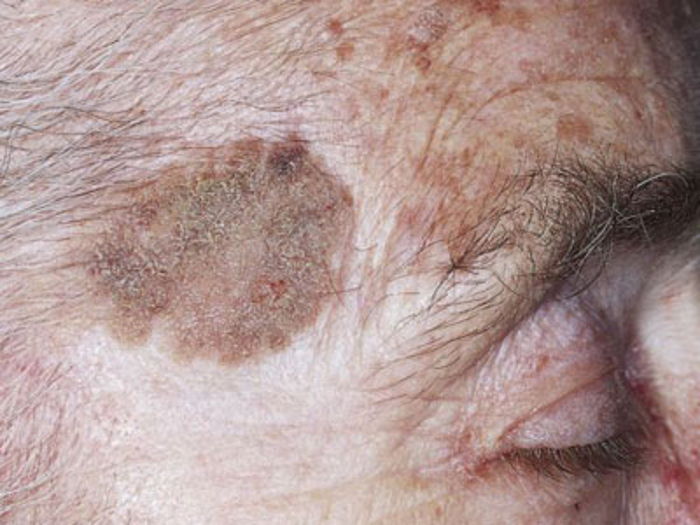

- 7. DERİNİN PREKANSERÖZ LEZYONLARI

7. DERİNİN PREKANSERÖZ LEZYONLARI